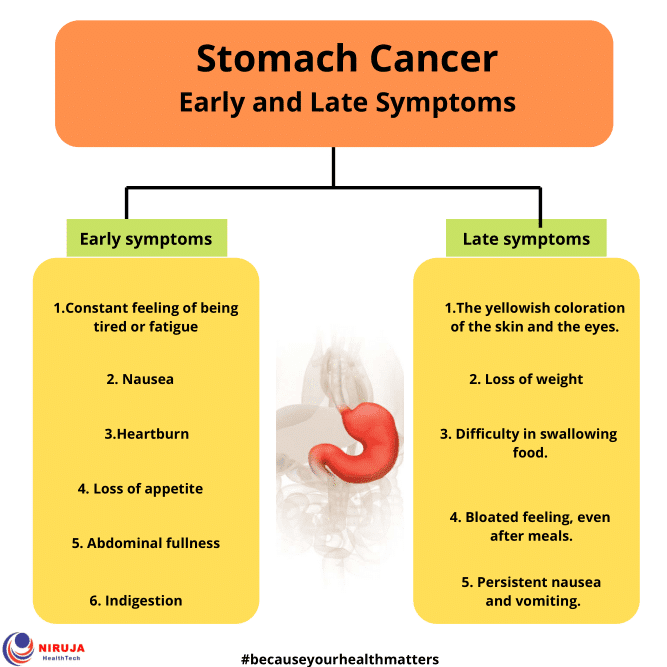

Early Symptoms of Stomach Cancer 胃癌的早期症狀(英文) | 衛教單張 – 中國醫藥大學附設醫院

Stomach Cancer: Early and Late Symptoms > Niruja HealthTech

Symptoms Of Stomach Cancer In Child – CancerWalls

Stomach Cancer: What You Should Know | IYTmed.com